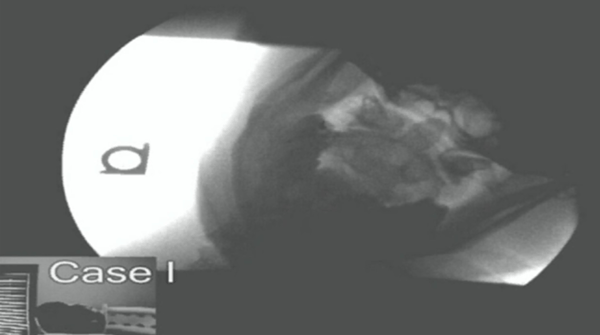

The next step involves the use of an imaging study called Digital Motion X Ray, or DMX that gives unprecedented insight into the biomechanics of the spine. DMX studies allow us to pinpoint the exact location and extent of damage to spinal ligaments.

DMX has been developed purely as a diagnostic tool, and uses imaging protocols that create a bright white background against which the bones are easily visible.

When you watch a DMX study, you are seeing an image of the patient in the lower left hand corner. You’ll see them move their head up and down, left and right, and side to side.

As the patient moves, DMX allows us to clearly visualize the movement of the bones in the spine. In patients who have suffered damage to the spinal ligaments, abnormal motion is present.

You will often see one vertebrae slide several millimeters in relation to another, indicating tearing of the anterior or posterior longitudinal ligaments.

The DMX allows these injuries to be clearly visualized by both an adjustor, defense counsel, and jury alike. It is very obvious to watch one bone literally slide off of another as someone flexes their head side to side.